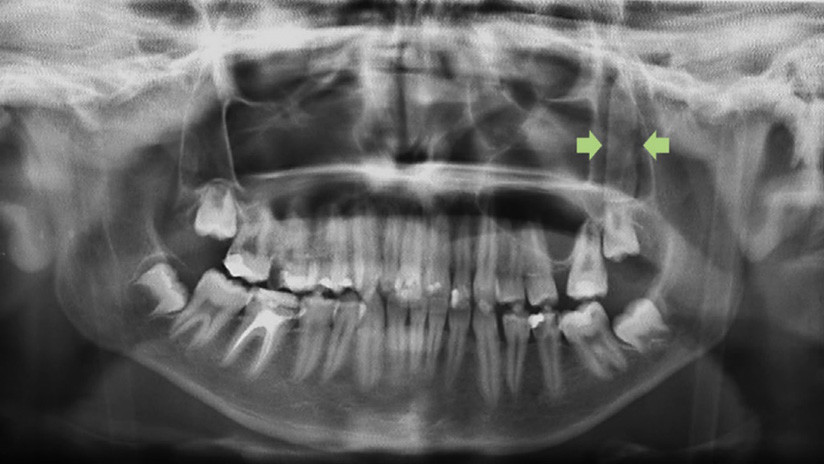

Fue a urgencias y una tomografía computarizada reveló que detrás de un pómulo tenía un objeto rectangular de 3,5 cm de longitud, con forma de hoja de cuchillo.